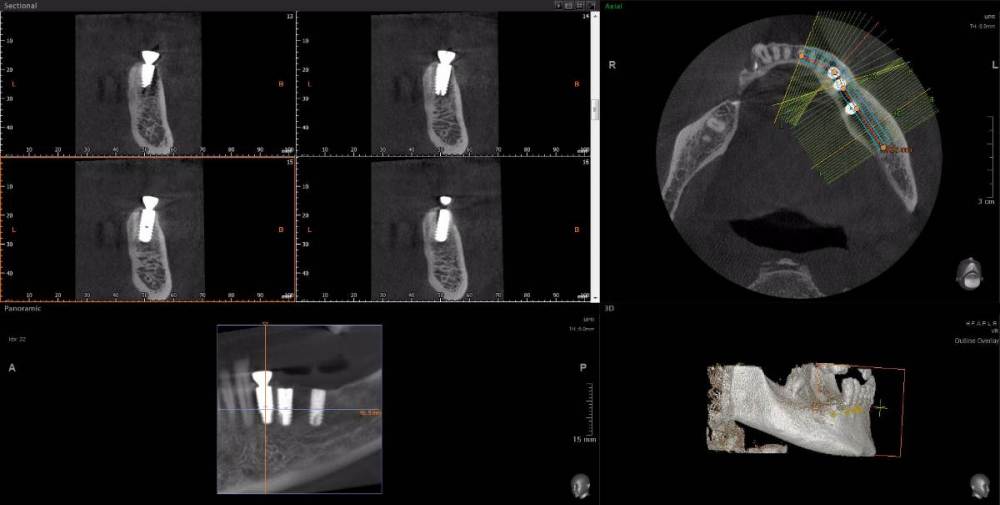

m-art-a23 Опубликовано 21 апреля, 2021 Поделиться Опубликовано 21 апреля, 2021 Здравствуйте. Два дня назад мужу установили 5 имплантов Ankylos на нижнюю челюсть (2+3). Спустя 30-40 мин после операции появилась сильная острая боль, которая не уменьшается по настоящее время. Боль похожа по ощущениям на пульпитную, не снимается никакими НПВС, кроме кеторолака. А/б, А/гистаминные, холод местно, хлоргексидин - все рекомендации выполнялись. На осмотре врачом не обнаружено следов воспаления, КТ сделал - без особенностей. Что может служить причиной такой боли, сколько она может длиться и что делать в данной ситуации? Врач-имплантолог ничего внятного не предложил. Ссылка на КТhttps://cloud.mail.ru/public/EvKn/ULqxLy6BD Ссылка на комментарий

wladdX Опубликовано 21 апреля, 2021 Поделиться Опубликовано 21 апреля, 2021 (изменено) Вы не указали локализацию болей, слева или справа? Левая сторона Справа Изменено 21 апреля, 2021 пользователем wladdX 1 Ссылка на комментарий

red_butler Опубликовано 22 апреля, 2021 Поделиться Опубликовано 22 апреля, 2021 7 минут назад, m-art-a23 сказал: Нет, не один. Но он лучший. Скажите пожалуйста, что служит причиной боли, по-Вашему? Неужели все импланты нужно убирать только по Кт трудно судить, но есть вопросы по позиционированию имплантов... боль может быть вызвана перегревом кости во время формирования ложа импланта, но в этом случае она появляется примерно с третьего дня. Так же боль может вызывать гиперкомпрессия импланта, и может болеть кость если ее придавили формирователем десны. Я бы обсудил с хирургом удаление среднего импланта слева 1 Ссылка на комментарий

Irouil Опубликовано 22 апреля, 2021 Поделиться Опубликовано 22 апреля, 2021 Я бы рекомендовал удаление среднего импланта слева, независимо от наличия/отсутствия болевых ощущений боль может быть признаком каких-то описанных моим коллегой процессов, а может ничего кроме самой боли не означать (менее вероятно, но и такое бывает). Если удаление упомянутого импланта поможет против болевого синдрома - это win-win если хирург не видит необходимости удаления импланта, я бы рекомендовал сходить на осмотр к ортопеду, который будет в будущем эти импланты протезировать. Возможно у него найдутся весомые аргументы для коллеги 3 Ссылка на комментарий

Irouil Опубликовано 22 апреля, 2021 Поделиться Опубликовано 22 апреля, 2021 (изменено) 1 час назад, m-art-a23 сказал: Благогдарю за совет. Если Вам не трудно, объясните пожалуйста, что не так со средним имплантом. Описанные процессы, если таковые имеют место быть, должны постепенно прийти в норму? Другими словами, сколько еще нужно времени, чтобы окончательно принять решение об удалении импланта (имплантов)? Сегодня третьи сутки после установки. Боль сохраняется. Средний имплант расположен чрезвычайно близко к соседнему, расположенному кпереди от него. С очень большой долей вероятности это может привести к значительной резорбции (убыли) костной ткани между ними, что для любых имплантов очень вредно, а для конкретно Анкилосов - губительно из-за особенностей их протезирования. Если неблаготворные процессы (компрессионный или термический некроз) присутствуют, то импланты просто не интегрируются (не приживутся) - те, что зашиты не выдержат нагрузки при раскрытии, а тот, на котором стоит ФДМ - расшатается через 2-3 недели. Это не призыв проверять его стабильность языком, сейчас его лишний раз лучше не трогать. В норме после имплантации боли держатся 1-2 дня, если все не очень хорошо - держатся 2-3 недели, но даже в таком случае имплант может интегрироваться, поэтому решение об его удалении в таком случае должно, по моему убеждению, быть совместным между врачом и пациентом, и приниматься в индивидуальном порядке Изменено 22 апреля, 2021 пользователем Irouil Ссылка на комментарий